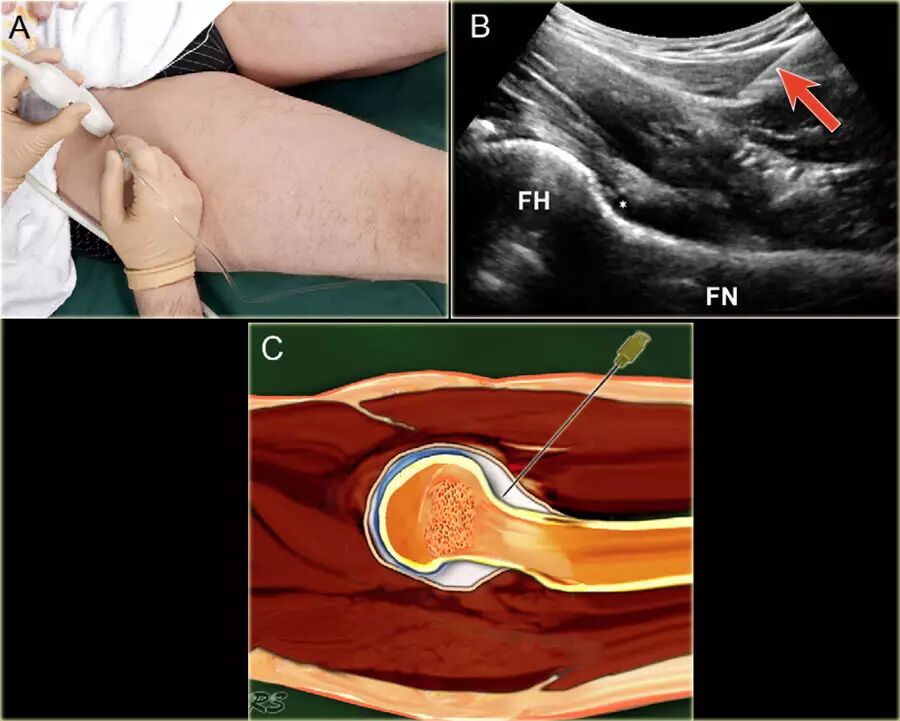

髋关节

患者仰卧。腿被保持在微小的内旋和外展,从而缓和局部囊结构的紧张使髂腰肌腱和囊在中心移出预期的针路径。优选地,使用5-3.5MHz的弯曲阵列换能器,其提供必要的穿透深度。通常,对于平均成年人使用长度为9cm的21号针。 在较小的成人或儿童中,可以使用23号5cm皮下注射针。

局部麻醉剂可以在主要注射之前注射,但是这需要额外的操作以及在关节中的非造影流体(麻醉剂)留下较少的空间,使有限的关节空间更小,以及可能的2个穿刺。

可以通过在包含麻醉剂和注射流体(对比剂或药物)的两个注射器之间使用三通连接器,来避免麻醉后换造影剂时引起的以外的脱针。